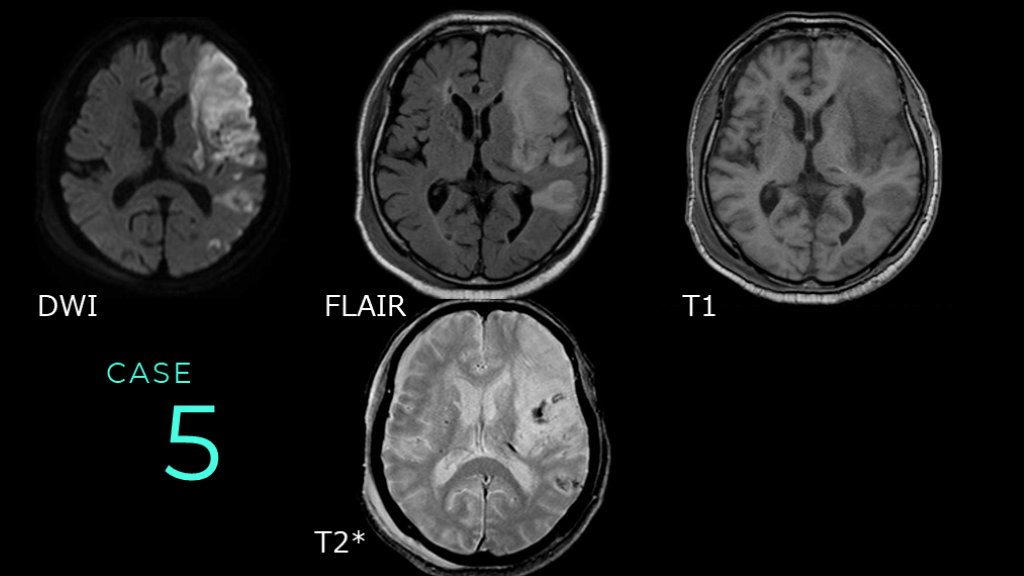

CASE 5 DWI FLAIR T1 T2*

CASE 5 DWIでは左の前頭葉を中心に、皮質を含んだ白質に広範な高信号病変を認める。同病変はFLAIRでHIGH、T1WIでLOWである。数日経過した亜急性期の脳梗塞病変疑いである。 DWI FLAIR T1

CASE 5 T2*では、DWIでの信号変化を認める病変の内部に低信号病変を認め、出血病変の合併が示唆される。 DWI T2*

CASE 5 DWI→FLAIR→T1まで信号変化を認めるので、時間のたった脳梗塞病変だとわかる。また、T2*で出血病変が指摘できた。T2*がなければ判断は難しいので、ここでは出血性病変の指摘にT2*が役に立った。 DWI FLAIR T1 T2*